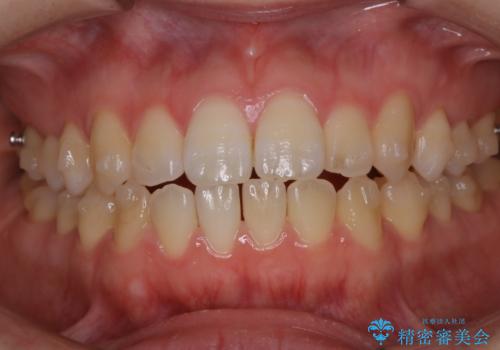

アタッチメント周囲のステインOFFをPMTC で

- インビザライン矯正治療中に、アタッチメント周囲のステインが気になるとのことでした。PMTC30分コースを行いました。